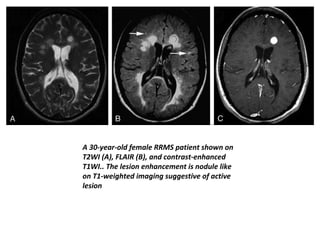

• On T1-weighted imaging (T1WI), the acute MS lesions

are often isointense to the normal white matter but

can be hypointense if chronic tissue injury or severe

inflammatory edema occurs.

• In the acute inflammatory phase, the lesion may

disrupt the BBB, leading to gadolinium enhancement

that is believed to be the first detectable event on

conventional MR imaging,and may last from days to

weeks. The longer the wait the more enhancement

will be seen on the T1W images.

• Enhancing lesions, which may vary in shape and size;

usually start as homogeneous enhancing nodules and

subsequently progress to ringlike enhancements.

A 30-year-old female RRMS patient shown on

T2WI (A), FLAIR (B), and contrast-enhanced

T1WI.. The lesion enhancement is nodule like

on T1-weighted imaging suggestive of active

lesion